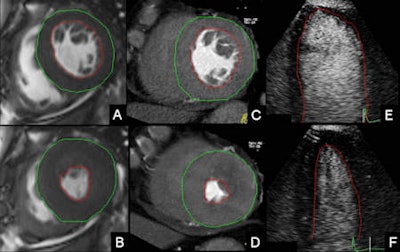

Left ventricular (LV) manual contour tracing for the assessment of LV parameters in cardiac MRI (CMR), cardiac dual-source CT (DSCT) and 2D contrast-enhanced echocardiography (CE echo). A, B: CMR short-axis views. C, D: Cardiac DSCT short-axis views. E, F: Two-dimensional CE echo apical four-chamber views. A, C, E: End diastole. B, D, F: End systole. Images courtesy of Dr. Maria Arraiza.Evaluation of patients who have undergone heart transplants requires early detection of graft vasculopathy and accurate assessment of cardiac volumes, function, and mass so as to improve graft outcomes and increase patient survival, the study team noted in an article-in-press published online on 4 May.